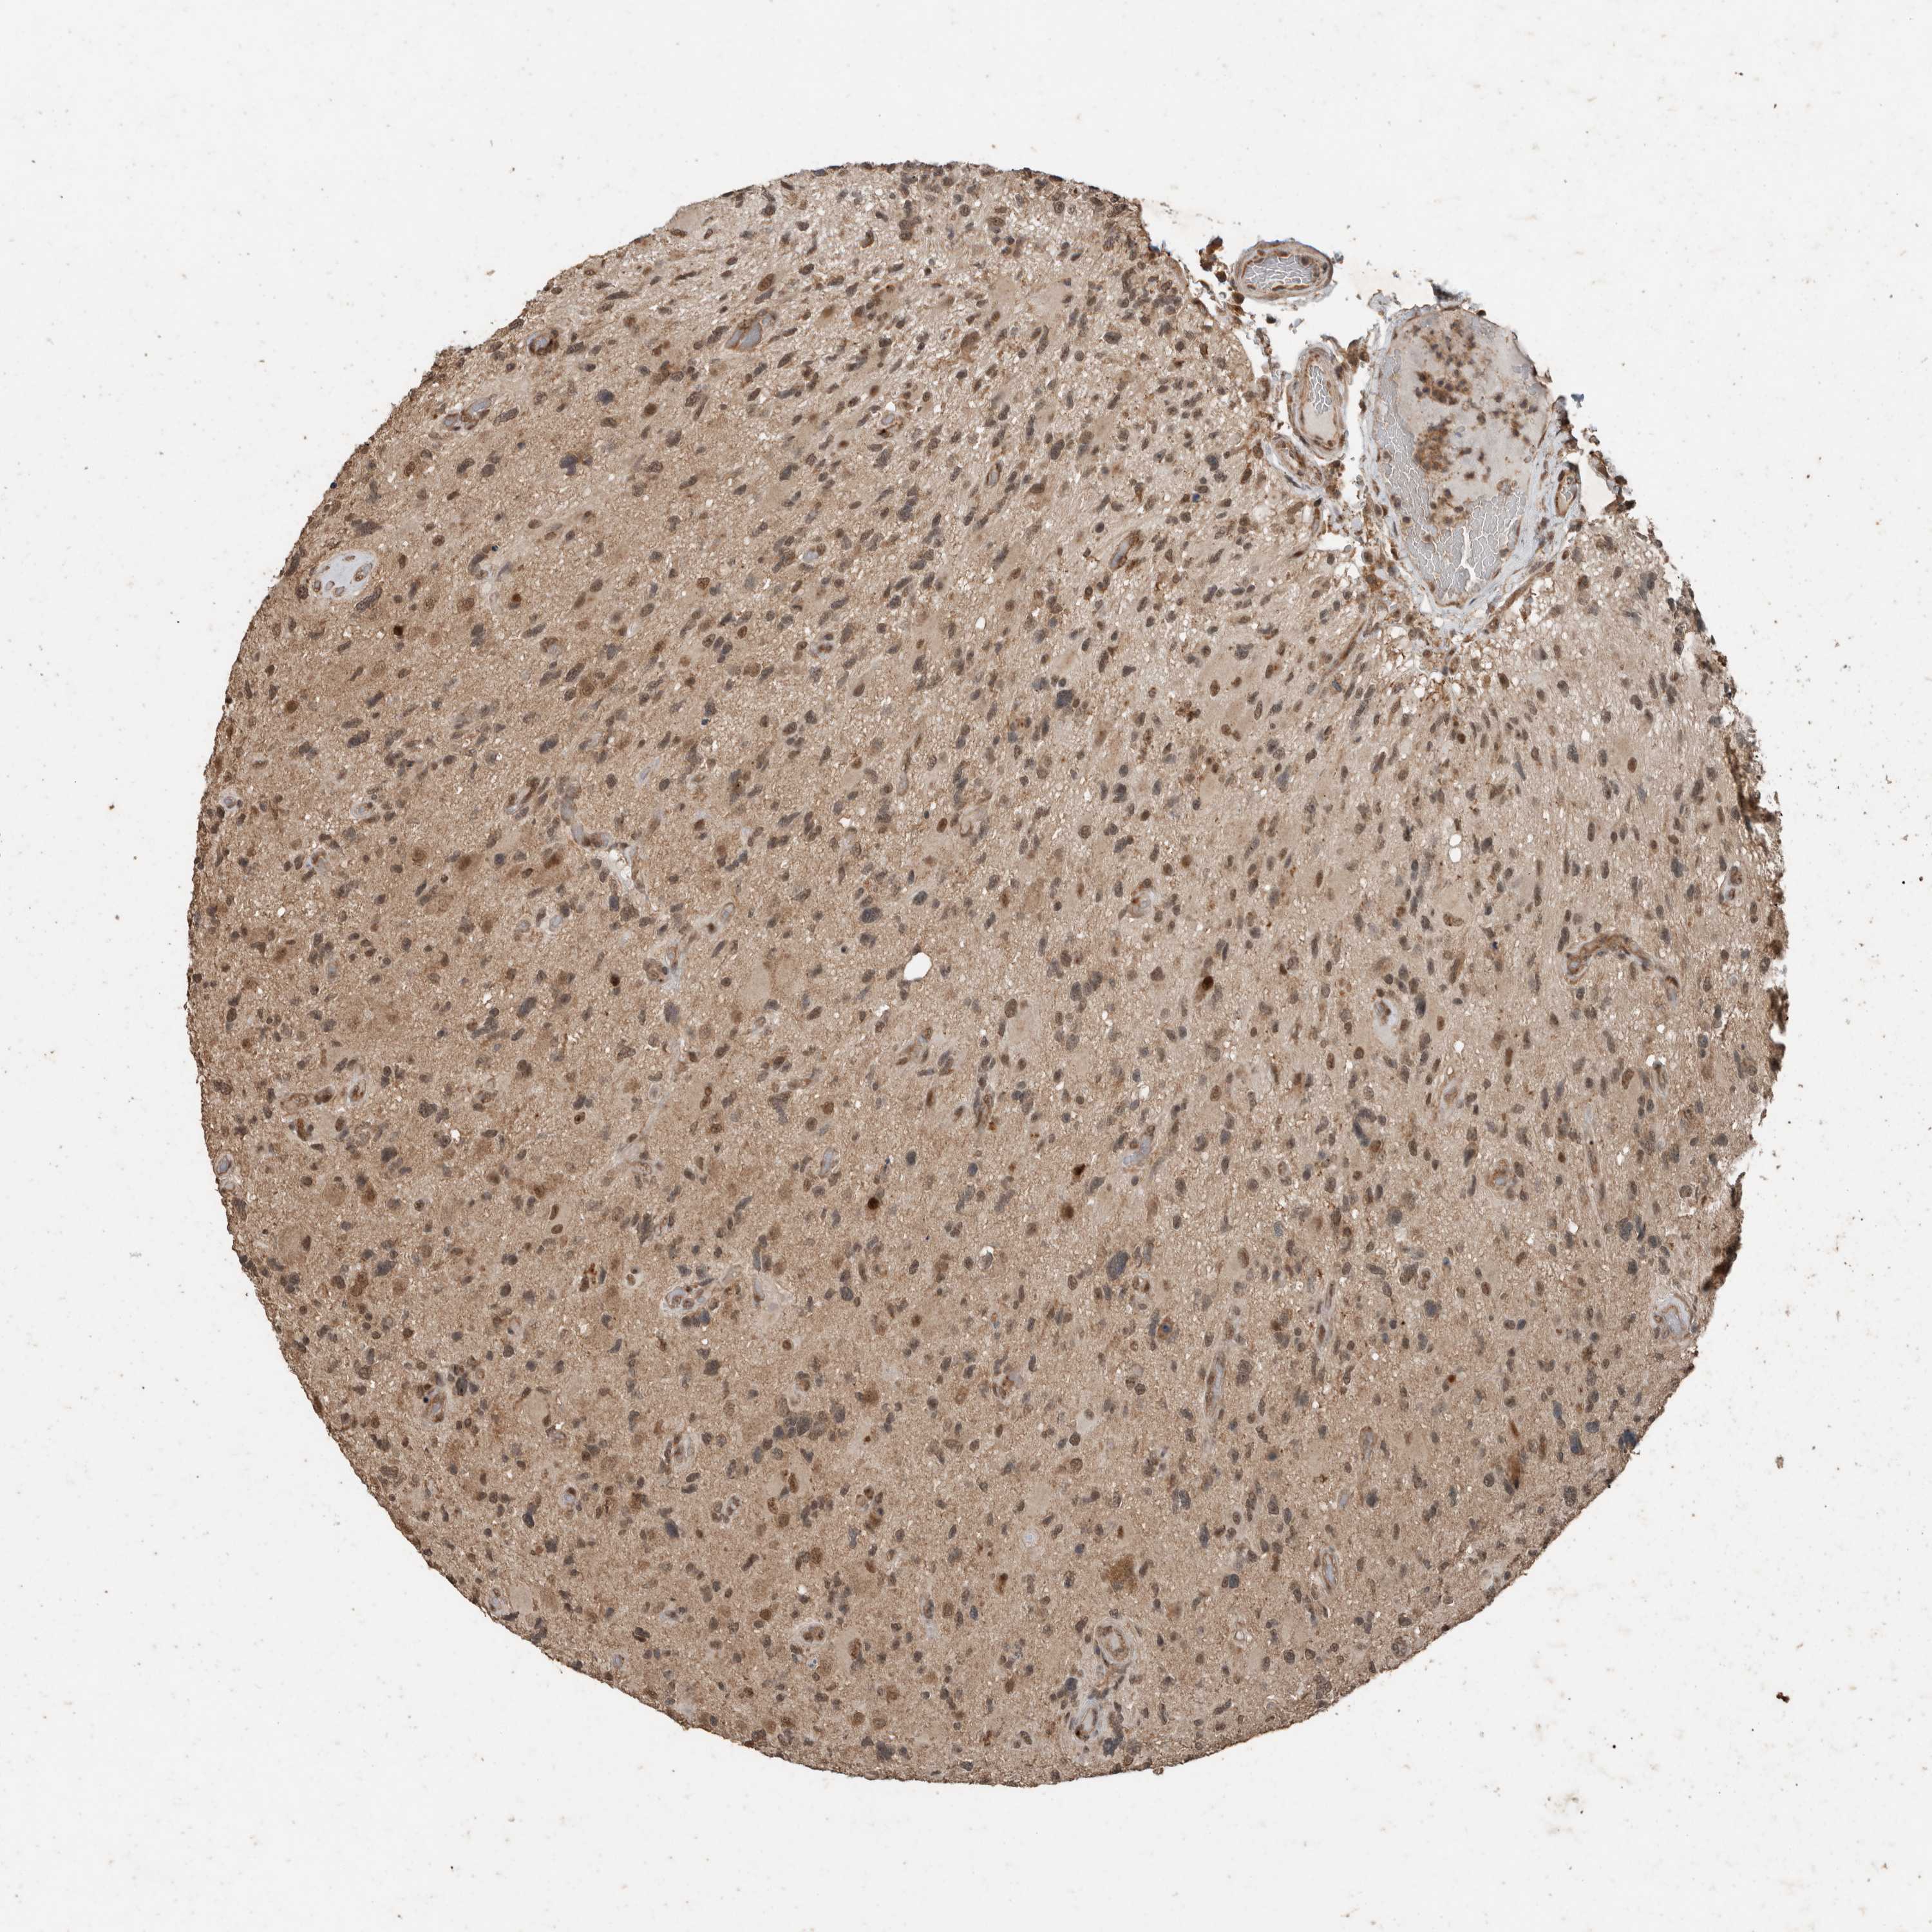

GLIOMA - Protein expressioni

A mouse-over function shows sample information and annotation data. Click on an image to view it in a full screen mode. Samples can be filtered based on level of antibody staining by selecting one or several of the following categories: high, medium, low and not detected. The assay and annotation is described here.

Note that samples used for immunohistochemistry by the Human Protein Atlas do not correspond to samples in the TCGA dataset.

Antibody stainingi

Antibody staining in the annotated cell types in the current human tissue is reported as not detected, low, medium, or high, based on conventional immunohistochemistry profiling in selected tissues. This score is based on the combination of the staining intensity and fraction of stained cells.

Each image is clickable and will lead to virtual microscopy that enables deeper exploration of all samples and also displays staining intensity scores, fraction scores and subcellular localization as well as patient and tissue information for each sample.

Antibody HPA023886

Staining

High

Medium

Low

Not detected

Intensity

Strong

Moderate

Weak

Negative

Quantity

>75%

75%-25%

<25%

None

Location

Nuclear

Cytoplasmic/membranous

Cytoplasmic/membranous,nuclear

Glioma, malignant, High grade

Glioma, malignant, Low grade